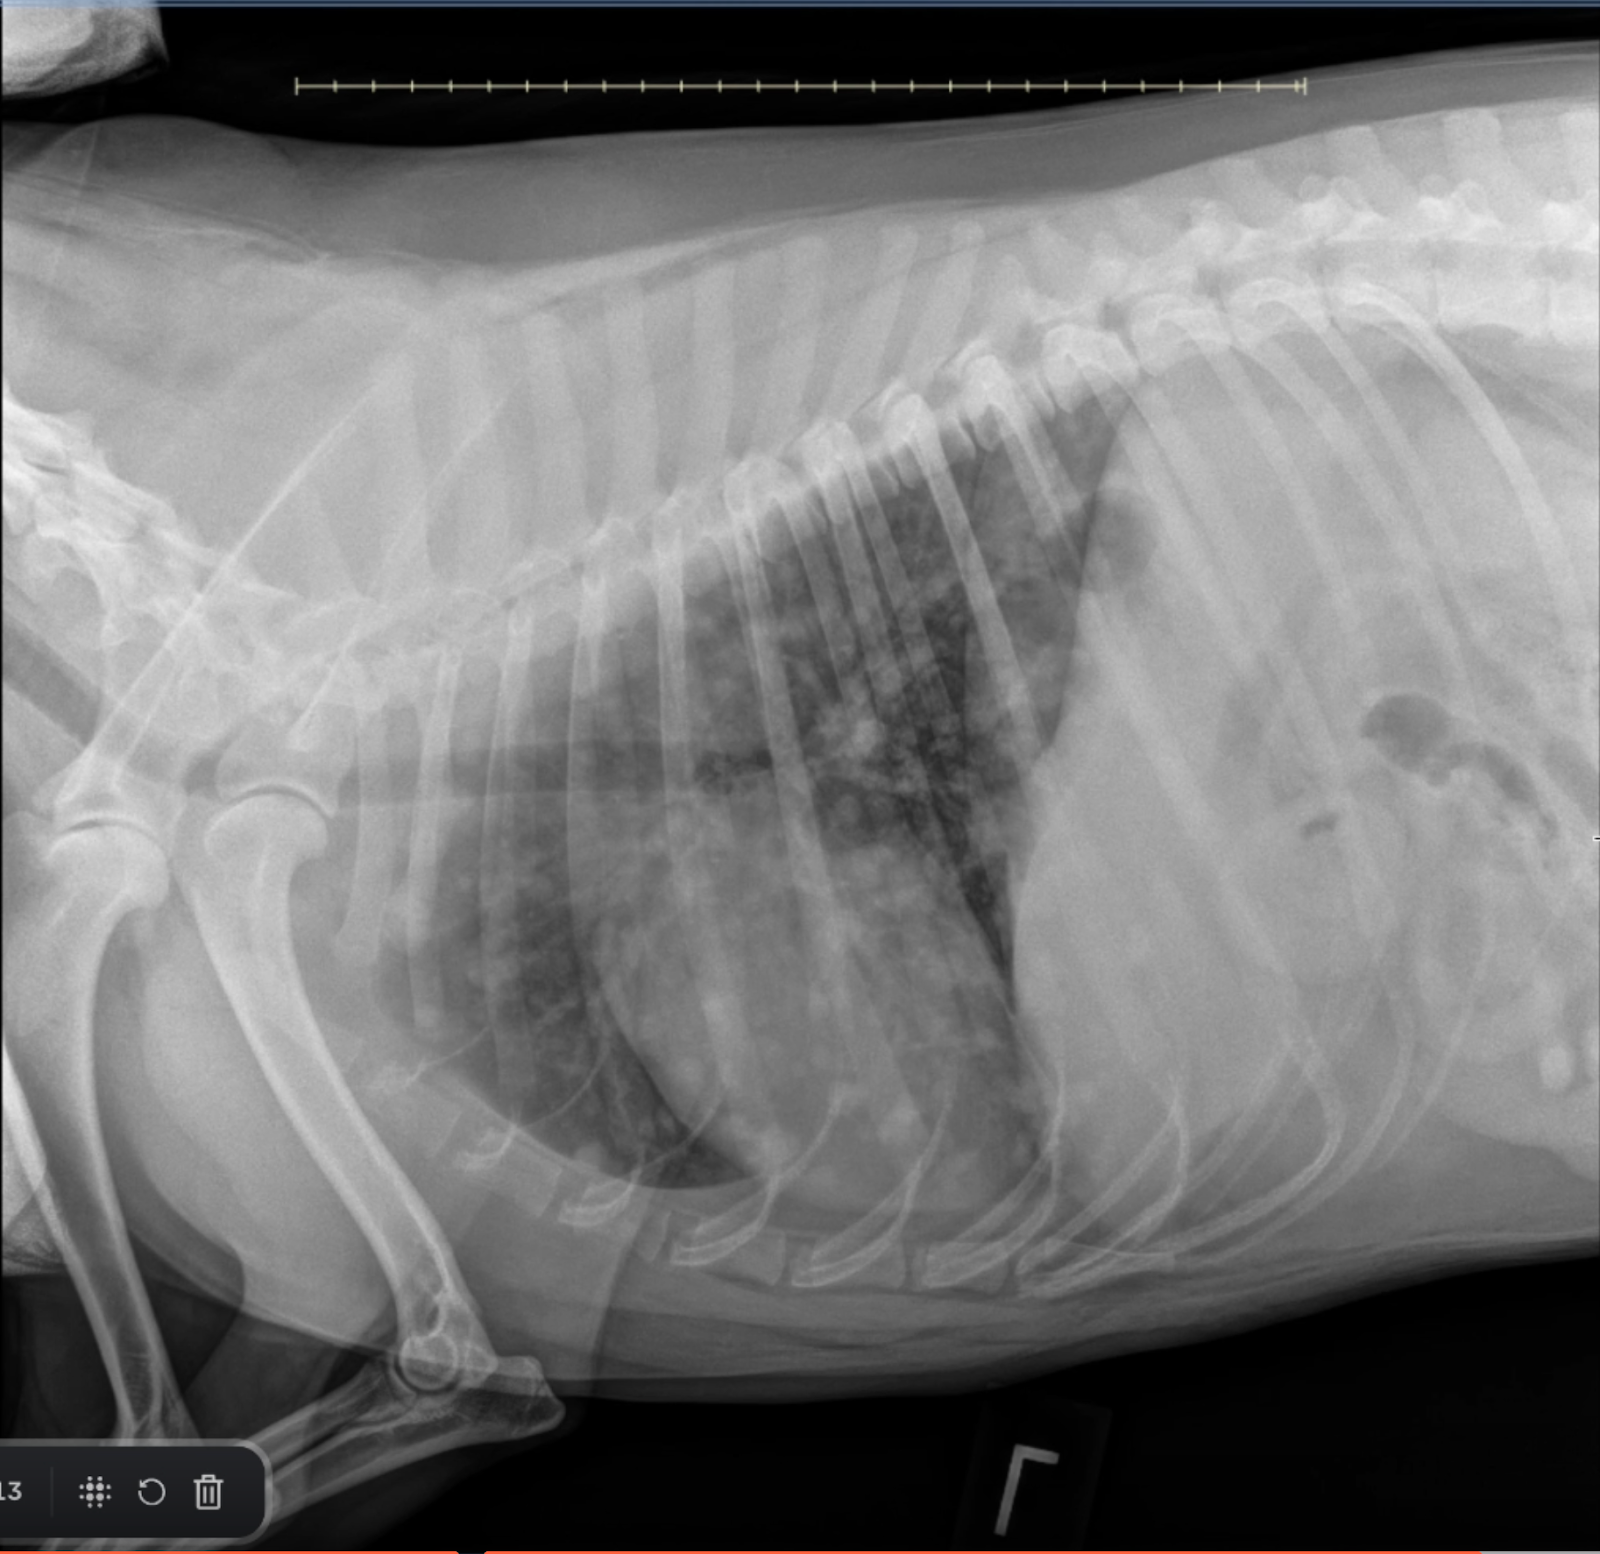

Radiographic Assessment:

Image 1: Ventrodorsal (VD) View

• Cardiovascular and Mediastinal Structures: The caudal vena cava enters the cardiac silhouette normally at the cardiac waist. No left atrial or ventricular enlargement is identified. The trachea is appropriately deviated ventrally, consistent with normal heart size.

• Pulmonary Parenchyma: Multiple discrete soft tissue nodules are visible throughout the lung fields, including peripheral regions, confirming that these are parenchymal in origin and not artifacts of summation or vascular overlap.